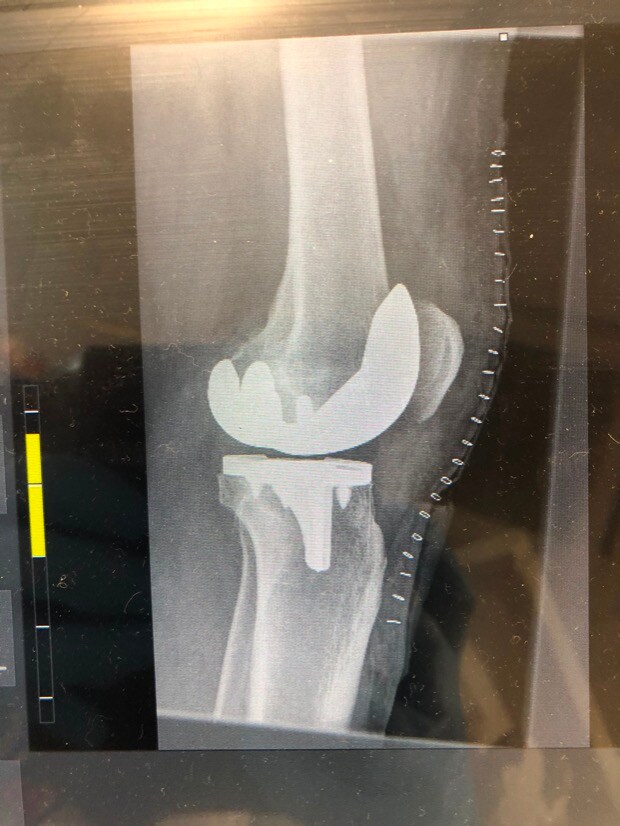

1. Evening TT’ers I’m one week into recovery from having total knee replacement surgery on my left knee. I’m wondering if anyone else out there has had the same surgery and can provide some advice on how long it took after surgery before you were back on the golf course or at least swinging a club. Are there any pitfalls I should avoid? All advice welcome including tongue in cheek to cheer me up!!! Cheers………..Steve

Post Image

3. Stephen, I've been there - I've got similar X-rays, though mine have random bits of metal from earlier ACL's. Right knee for me. Right knee is "better" as the loading through the swing is more intense on the left knee for right handers. One week in can be a low point. No point in being a hero - take whatever painkillers they give you!! Stairs will be an issue for some considerable time I'm afraid. You will, however, be able to use stairs to strengthen your muscles. Be diligent about your physio and to get access to an exercise bike of some description! When allowed, I did lots of walking and found it helped. I had my op in the November and was ready for the Driving Range the following March. Some say they were back on the golf course six weeks after the op - I would consider that to be a very risky strategy. It's a major reconstruction and it takes time to heal. The numbness wears off eventually but don't expect it to be exactly like a natural knee - it's good, but it's not that good! Oh, and be prepared to be stopped by Security at every airport - You'll set of the metal detector alarms!!